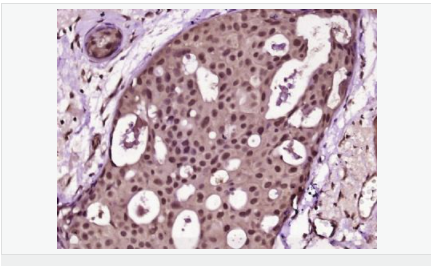

| 产品应用 | ELISA=1:5000-10000 IHC-P=1:100-500 IHC-F=1:100-500 Flow-Cyt=1μg/Test (石蜡切片需做抗原修复) not yet tested in other applications. optimal dilutions/concentrations should be determined by the end user. |

| 产品介绍 | Proliferation Marker Ki67 antigen is the prototypic cell cycle related nuclear protein, expressed by proliferating cells in all phases of the active cell cycle (G1, S, G2 and M phase). It is absent in resting (G0) cells. Ki67 antibodies are useful in establishing the cell growing fraction in neoplasms (immunohistochemically quantified by determining the number of Ki67 positive cells among the total number of resting cells = Ki67 index). In neoplastic tissues the prognostic value is comparable to the tritiated thymidine labelling index. The correlation between low Ki67 index and histologically low grade tumours is strong. Ki67 is routinely used as a neuronal marker of cell cycling and proliferation. Function: Thought to be required for maintaining cell proliferation. Subcellular Location: Nucleus. Chromosome. Predominantly localized in the G1 phase in the perinucleolar region, in the later phases it is also detected throughout the nuclear interior, being predominantly localized in the nuclear matrix. In mitosis, it is present on all chromosomes. Similarity: Contains 1 FHA domain. SWISS: P46013 Gene ID: 4288 Database links: Entrez Gene: 4288 Human Entrez Gene: 17345 Mouse Omim: 176741 Human SwissProt: P46013 Human SwissProt: Q91VE6 Mouse Unigene: 689823 Human Unigene: 80976 Human Unigene: 4078 Mouse Unigene: 233802 Rat Important Note: This product as supplied is intended for research use only, not for use in human, therapeutic or diagnostic applications. 细胞增殖标志物(Proliferation Marker) Ki67与PCNA一样,为细胞增殖的一种标记,在细胞凋亡中S、G2 、M期均有表达,G0期缺如。 Ki-67增殖指数高低与许多肿瘤的分化程度、浸润、转移以及预后密切相关,因此被广泛作为各种恶性肿瘤的必检项目之一。 |